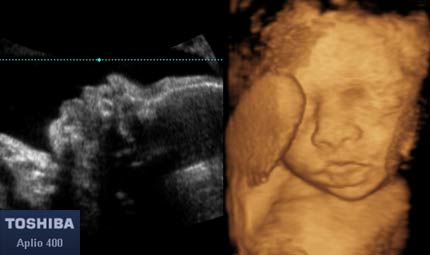

Sett 25, profilo e volto 3d © Dr. Maurizio Longo, DIAGNOSTICA PRENATALE